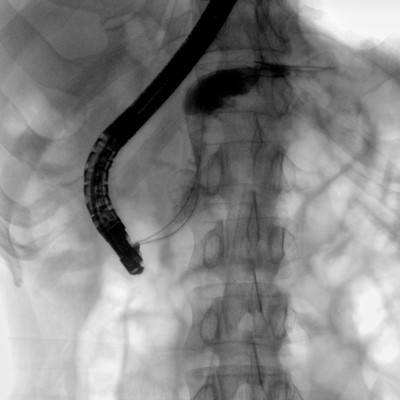

消化內(nèi)科: ERCP、PTCD、肝臟介入(TACE、灌注)、食管支架等。

優(yōu)質(zhì)平板探測(cè)器、可靈活升降調(diào)節(jié)SID、獨(dú)特圖像處理系統(tǒng)、高品質(zhì)濾線柵,大視野成像清晰不失真。

采用智能劑量控制技術(shù),可根據(jù)不同體型和不同部位,準(zhǔn)確調(diào)節(jié)投照劑量。使操作者在任何使用環(huán)境下,都能實(shí)現(xiàn)低劑量、診視圖像清晰的效果。